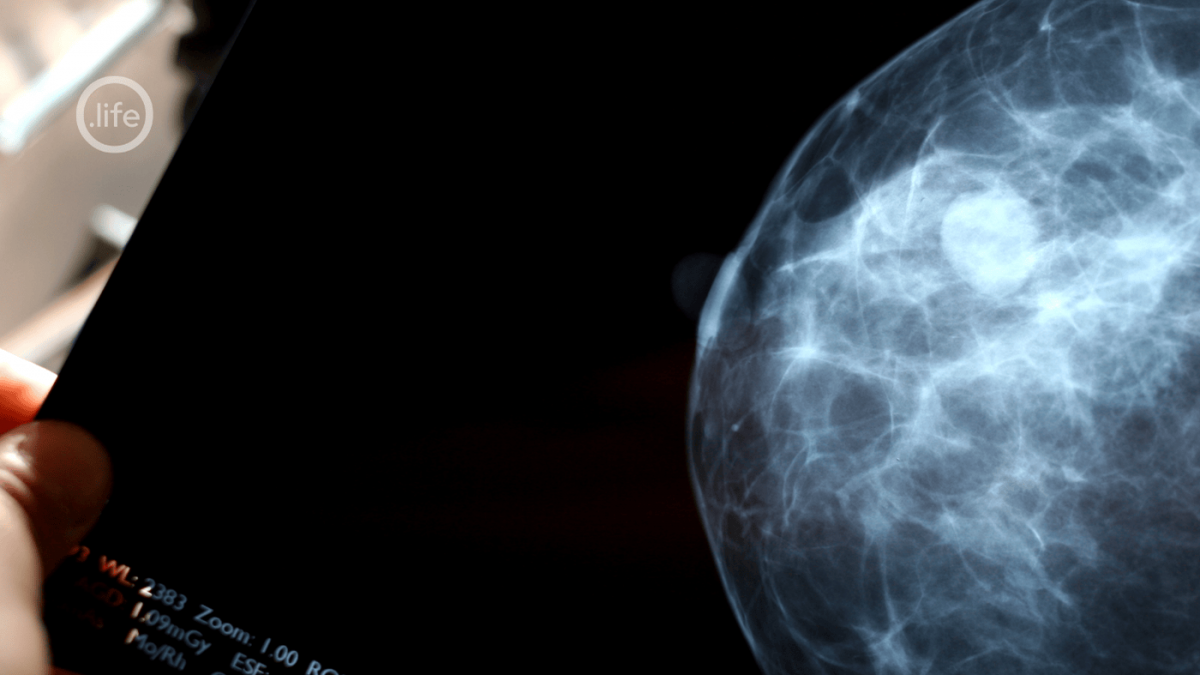

Warto to powiedzieć głośno: USG piersi bardzo często „coś pokazuje”. Zmiany ogniskowe, torbiele, zagęszczenia, asymetrie. U ogromnej części kobiet — zwłaszcza młodszych, z gęstą tkanką piersi — takie zmiany są wykrywane rutynowo i w przeważającej liczbie przypadków nie mają charakteru nowotworowego. To nie błąd badania. To jego dokładność. To też szansa na to, aby zmiany widzieć i obserwować, dając realną szansę na właściwą reakcję medycyny, we właściwym czasie. Tak jak u mnie – dwukrotny wzrost masy obserwowanego od dwóch lat guza = pogłębiona diagnostyka.

USG piersi i mammografia nie są konkurencją. Są dwoma różnymi językami opisu tego samego ciała. USG częściej prowadzi nas tam, gdzie pierś jest młoda, gęsta, hormonalnie aktywna. Mammografia bywa skuteczniejsza tam, gdzie struktura piersi się zmienia, a oko i głowica USG nie widzą wszystkiego.